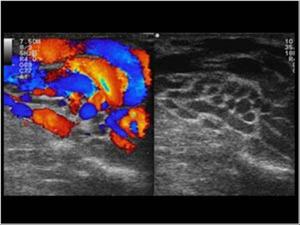

Varicocele